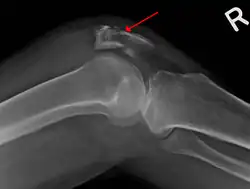

The patella can break in various ways depending on the way it is injured, and into two or more pieces.[1] Types include transverse, the most common, with one fracture line;[5] marginal; osteochondral; and the rare vertical type, or stellate, where a direct compression force gives rise to a comminuted pattern.[5][7] Patella fractures can be further classified as displaced, where the broken ends of bone do not line up correctly and separate by more than 2mm, or undisplaced and stable where pieces of bone remain in contact with each other.[1][7] If fragments of patella bone stick out from the skin it is known as an open patella fracture, and closed if the overlying skin is intact.[1]

Osteochondral fracture of patella -